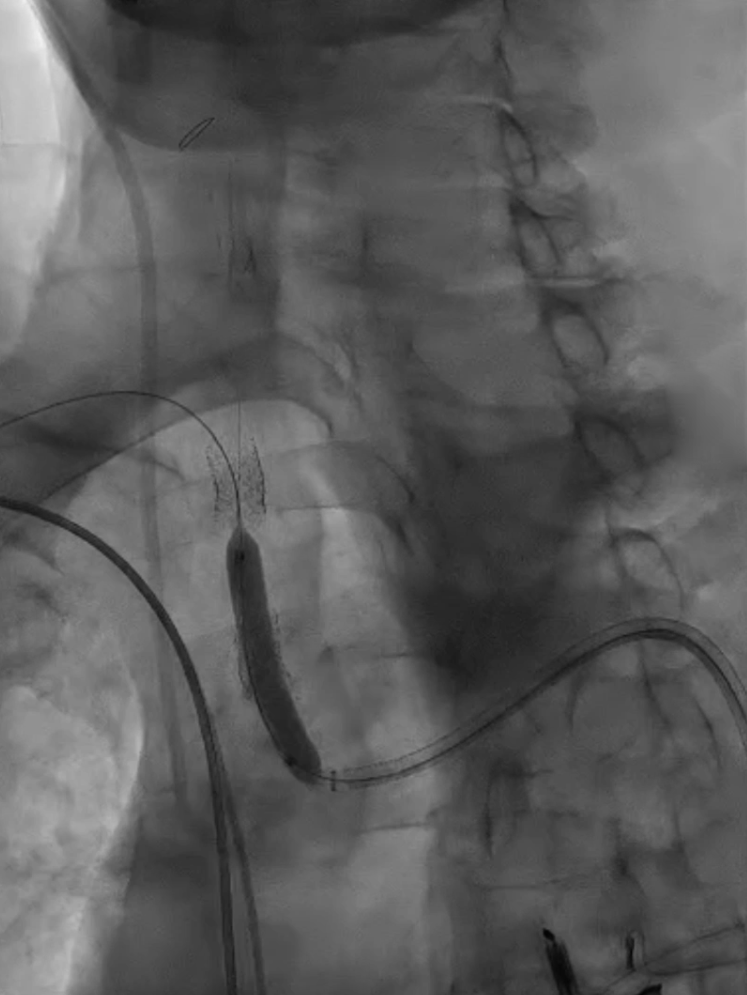

脑保护措施:更换加硬导丝后,采用Filterwire保护伞及0.018导丝选入右颈总动脉,进一步送入右颈内动脉释放保护伞。

跟进长鞘至无名动脉起始

Filterwire 3.5-5.5 保护伞

导丝选入右颈总动脉内

导丝选入右颈内动脉

放置保护伞